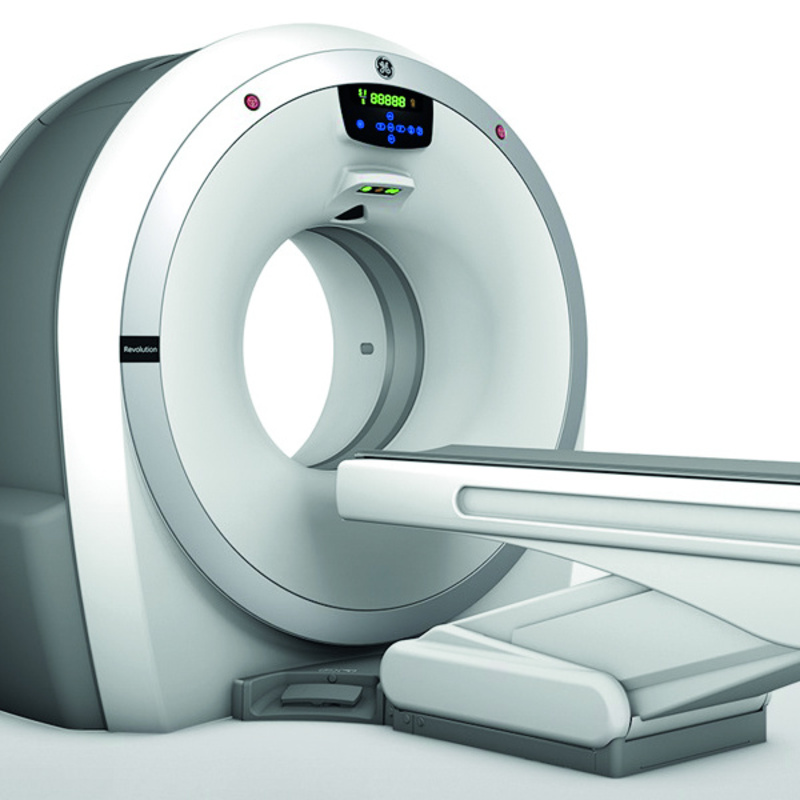

Revolution ACT

Revolution ACT è il tomografo computerizzato di ultima generazione caratterizzato da un’estrema compattezza, abbinata a un’elevata qualità delle immagini, notevole velocità di scansione e a diminuzione della dose di radiazioni erogate ai pazienti.

Descrizione prodotto

Migliora le tue prestazioni

Progettato pensando alle tue esigenze, Revolution ACT ti aiuta a migliorare gli standard di cura del paziente fornendoti nuovi livelli di qualità dell'immagine, tutela del paziente, performance economiche e applicazioni avanzate. Il risultato di questi progressi è racchiuso in un ventaglio di tecnologie integrate e in gran parte esclusive da oggi a tua disposizione.

Le tue aspirazioni. Realizzate.

Revolution ACT, a “geometria corta”, garantisce diagnosi più rapide e più precise:

- TAC a 16 strati ad elevata velocità di scansione grazie all’innovativa funzione IQE Pitch Booster

- Pannello detettore Clarity basato sull’innovativa tecnologia dei pannelli a design segmentato

- Risoluzione spaziale di 18 lp/cm per consentire l’imaging di alta qualità e la visualizzazione dell’anatomia in 3D

- Ricostruzione con Overlap* per una migliore qualità e fedeltà dell’immagine grazie all’algoritmo di ricostruzione del fascio iconico di GE

- Adaptive Enhance Level Adjustment che migliora la risoluzione spaziale visiva